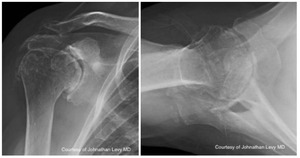

Case four is a 63-year-old retired nurse who was very active with weight lifting, horseback riding, tenis, and yoga. Surgical history included two prior arthroscopid debridements and capsular release. His pre-operative Subjective Shoulder Value (SSV) was 30% and pain score was 10/10. Exam showed 140° of active forward flexion, 30° of active external rotation, and active internal rotation to the sacrum. Radiographs (Figure 11) and CT (Figure 12) scan showed end stage arthritic changes without significant glenoid deformity. Options were discussed with the patient and due to his relatively young age and activity level, an inlay glenoid component was selected. This was combined with mild high side reaming. Radiographs at one year show a well seated component without signs of loosening or failure (Figure 13). Postoperative SSV was 95% and he returned to all prior activities (Figure 14).